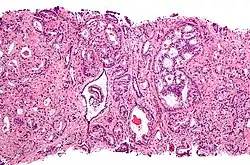

Рак предстательной железы

Для развития и целостного функционирования предстательная железа нуждается в андрогенах. Врождённая дисфункция андрогенового рецептора или 5-альфа-редуктазы у мужчин приводит либо к полному отсутствию, либо лишь к минимальному развитию предстательной железы. То же самое верно и для самцов других животных. Через неделю после кастрации предстательная железа самца крысы подвергается дегенерации из-за апоптоза эпителиальных клеток (после удаления семенников уровень андрогенов недостаточен для поддержания целостности простаты). Андрогены также относятся к факторам, стимулирующим развитие рака предстательной железы. Изучение евнухоидных индивидуумов показало, что у них простата остаётся маленькой и не подвергается гипертрофии или злокачественному перерождению. Более того, в животных моделях канцерогенеза в предстательной железе необходимо наличие семенников или экзогенных андрогенов для поддержания развития опухоли. У трансгенных мышей с повышенной экспрессией AR в простате клетки эпителия простаты обновляются гораздо быстрее, чем в норме, и простатическая интраэпителиальная неоплазия (злокачественное новообразование) у таких мышей появляется значительно раньше. Хотя необходимость андрогенов для развития рака простаты не вызывает сомнений, сложно установить связь между относительным уровнем андрогенов в крови и риском развития рака простаты. Для объяснения различий в частоте возникновения и степени выраженности рака простаты были предложены расовые различия в уровне циркулирующих в крови андрогенов. Впрочем, данные по связи между уровнем андрогенов в крови и риском развития рака предстательной железы весьма противоречивы, и окончательного решения по этому вопросу нет. Возможно, противоречивость данных объясняется варьирующей активностью андрогеновых рецепторов, которая может играть исключительно важную роль в развитии рака простаты[10].

Показано, что генетическое разнообразие в локусе AR связано с риском рака простаты. В частности, установлено, что количество повторов в области CAG-повторов обратно связано с активностью AR. Проявление этого на клеточном уровне тканеспецифично из-за того, что полиглутаминовый участок в N-концевом домене оказывает влияние на взаимодействие рецептора с p160 и другими коактиваторами. В различных исследованиях было показано, что чем короче участок CAG-повторов в N-концевом домене AR, тем агрессивнее опухоль, раньше начало развития рака и выше вероятность рецидива. Впрочем, в других исследованиях получены иные данные. С риском рака простаты связывают и другие изменения в AR, например, в 5'-нетранслируемой области, но объяснения этим связям пока ещё нет. В отличие от синдрома нечувствительности к андрогеном, для которого было определено множество вызывающих мутаций, мутаций, обусловливающих предрасположенность к раку простаты, немного. Впрочем, одна такая наследуемая мутация (миссенс-мутация) была обнаружена в Финляндии[10].

В клетках рака простаты ген AR иногда подвергается различным изменениям. Было установлено, что клетки рака простаты, как и клетки эпителия простаты, из которых они произошли, сохраняют необходимость в андрогенах, и в условиях недостатка андрогенов погибают. В самом деле, в 80 % случаях клетки рака простаты реагируют на отсутствие андрогенов. Однако в условиях терапии, направленной на снижение уровня андрогенов (например, в результате кастрации), ген AR этих клеток может претерпеть определённые изменения. Так, у 25—30 % пациентов, подвергшихся такому лечению, ген AR претерпевает амплификацию, что увеличивает количество андрогеновых рецепторов в опухолевых клетках и помогает им выживать в условиях низкого уровня андрогенов. В других случаях изменения приводят к повышению чувствительности рецептора к эндогенным агонистам, позволяют ему распознавать более широкий спектр агонистов или уменьшают его чувствительность к антиандрогенам[10].